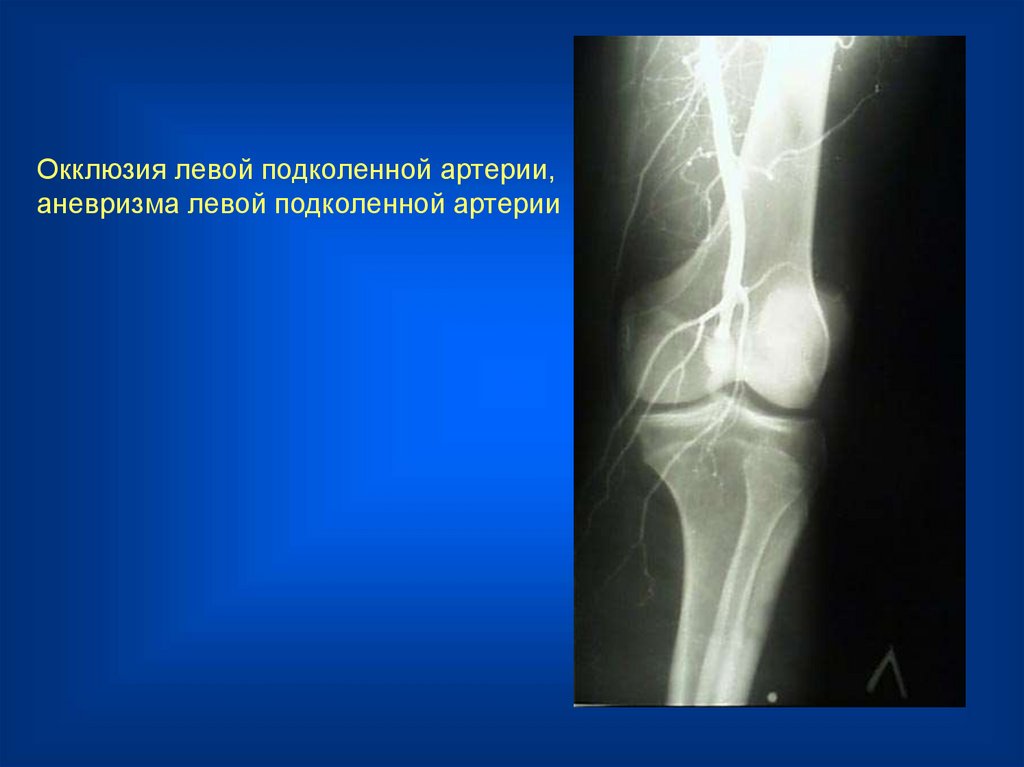

Окклюзия левой подколенной артерии,

аневризма левой подколенной артерии